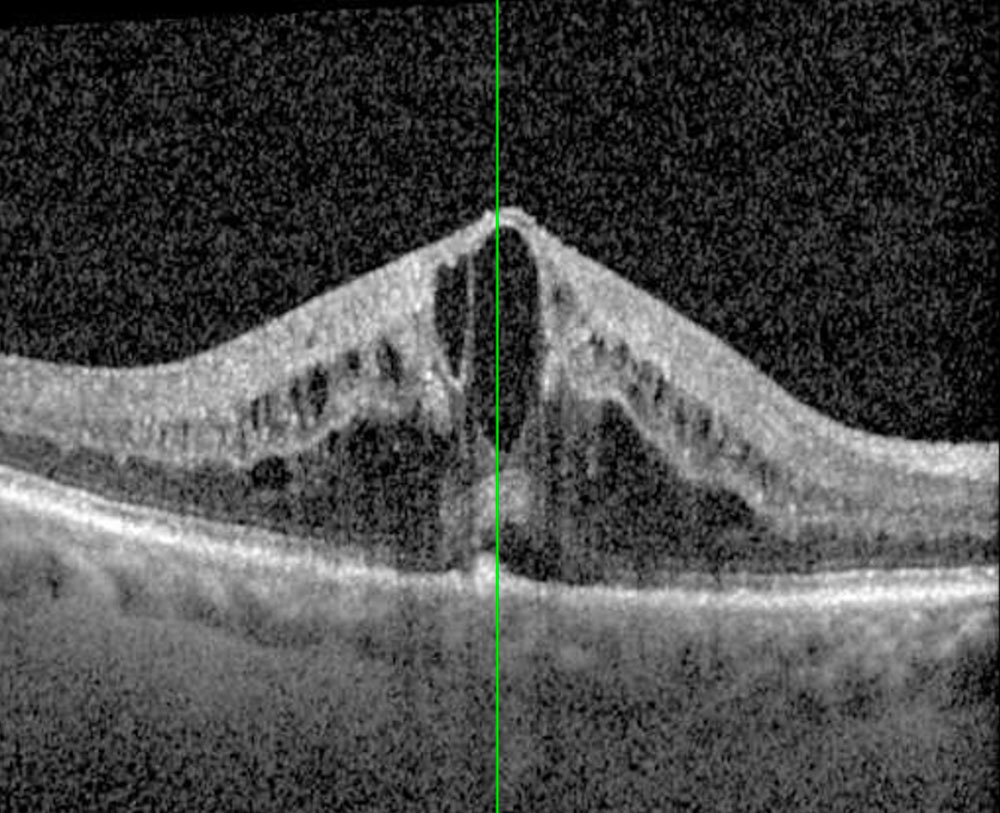

- OCT maculaire : quantification de l’œdème.